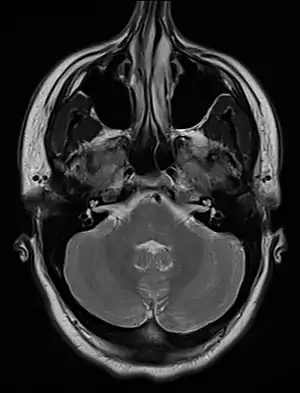

An MRI image showing a congenitally deviated nasal septum